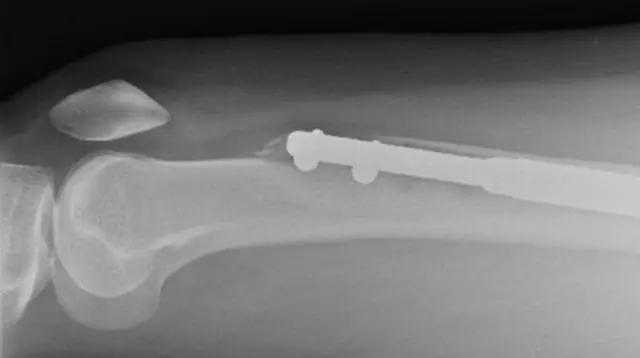

Wal’aansa kanaan walqabatee dhukkubbiin muraasni kanuma eegamudha. Yeroo baqaqsanii yaaluun gaggeefamu lafeen miila bakka lamatti cabee, sibiilli keessa galfama.

Sibiilli sun sududaan lafee lamaan addan dhiibe dheerina dabaluuf oola.

Qaawwa gidduutti uumamu guutuuf lafeen gargara cabe sududaan walitti deebi’ee fayyuu qaba. Oppireeshiniin kun walxaxaa waan ta'eef, adeemsa dheeraa qaba.

Ileeniin Siitii Iskaaniin, yaaddoo ishee mirkaneeffatte. Mismaarri miila ishee isa bitaa keessa jiru ni cabe.

Torban jaha booda, miila ishee mirgaa yeroo ilaalamtu haala rifaasisaa ta’een, lafee hin guddanne, jijjirama eegame hin agarsiisne.

Lafee naannoo tafa ishee sibiilaan walitti hidhame ture. Dubbiin akka isheen eegde hin taane.